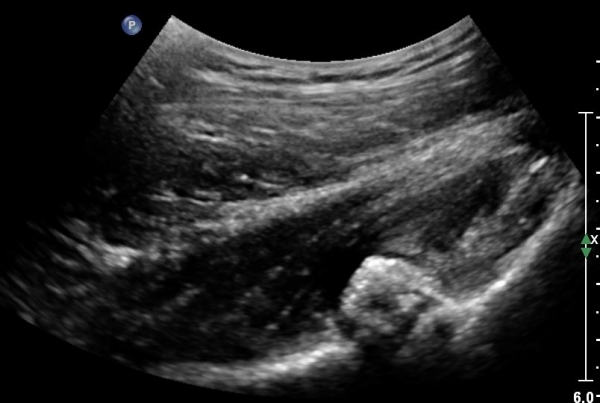

°í°üÀý ¿ÜÃø, ¹Ù·Î µÚ Á¾´Ü¸é°Ë»ç¿Í Ⱦ´Ü¸é °Ë»ç»ó °üÀý ¿Í¼øºÎÀ§¿¡ Ä¿´Ù¶õ °í¿¡ÄÚ ¼®È¸È­°¡ °üÂûµÊ(»çÁø 8, 9)